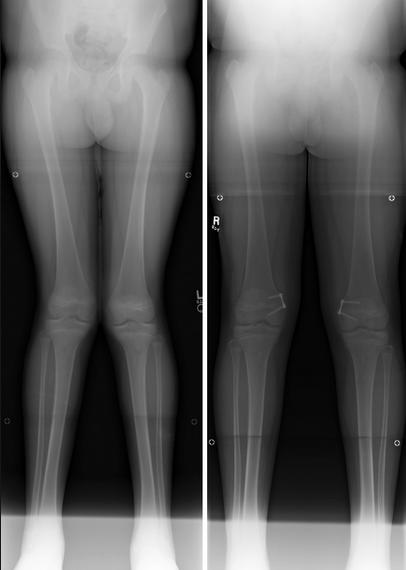

- Genu valgum is a normal physiologic process in children

- therefore it is critical to differentiate between a physiologic and pathologic process

- Normal physiologic process of genu valgum

- between 3-4 years of age children have up to 20 degrees of genu valgum

- genu valgum rarely worsens after age 7

- after age 7 valgus should not be worse than 12 degrees of genu valgum

- after age 7 the intermalleolar distance should be <8 cm